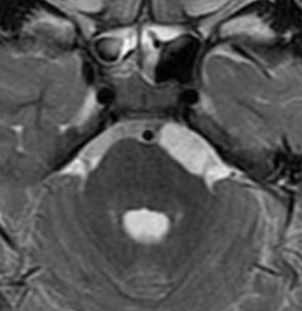

Эпидермоидные кисты (эпидермоиды) - доброкачественные врождённые образования. Они происходят из эктопических эпидермальных клеток и развиваются в период закрытия, в 3-5 нед. эмбриогенеза, как следствие неполного разделения нейрональной и покровной эктодермы. Частота составляет около 1% от внутричерепных образований. Обычно диагностируются в возрасте 25 - 45 лет. Локализация эпидермоидов может быть любой, но типичная - мосто-мозжечковый угол (третье по частоте образование этой области), предмостовая цистерна, параселлярная область, четверохолмие и желудочковая система, очень редко в полушариях, спинном мозге и интрадиплоидно. Растут они интра- или экстрадурально, экспансивно, медленно, сдавливая ствол мозга, внутричерепные нервы, но не разрушая кость. Иногда захватывают сосуды и нервы. По характеру роста их можно отнести к опухолевидным образованиям. Вокруг эпидермоидов нередко развивается асептическое воспаление, а при разрыве содержимое (жир, кератин) прорывается в ликворные пространства. Клинические проявления зависят от локализации и масс-эффекта.

При МРТ головного мозга картина неспецифическая и зависит от содержимого кисты. Если она не содержит жира, то имеет ликворную интенсивность сигнала . В таком случае эпидермоидная киста трудно отличима от арахноидальной, хотя, как правило, не столь однородная. На МРТ типа FLAIR и диффузионно-взвешенных МРТ изображениях содержимое эпидермоидов светлее ликворного. Жировое содержимое, такие эпидермоиды еще называют холестеатомой, приводит к высокому сигналу на Т1-взвешенных МРТ головного мозга. Видимо, он обусловлен липидами, но не холестеролом. На Т2-взвешенных МРТ головного мозга он менее интенсивен чем ликвор. Контуры эпидермоидов всегда четкие. Холестеатомы составляют всего 3-5% от эпидермоидов. В 15-20% случаев встречается кальцификация по переферии кисты. Редко наблюдается контрастирование стенок.

При МРТ головного мозга картина неспецифическая и зависит от содержимого кисты. Если она не содержит жира, топри МРТ головного мозга эпидермоидная киста имеет ликворную интенсивность сигнала. В таком случае эпидермоидная киста трудно отличима от арахноидальной, хотя, как правило, не столь однородная. На FLAIR томограммах и диффузионно-взвешенных МРТ головного мозга содержимое эпидермоидов светлее ликворного. Жировое содержимое, такие эпидермоиды еще называют холестеатомой, приводит к высокому сигналу на Т1-зависимых МРТ головного мозга. Видимо, он обусловлен липидами, но не холестеролом. На Т2-взвешенных МРТ головного мозга он менее интенсивен чем ликвор. Контуры эпидермоидов на МРТ всегда четкие. Холестеатомы составляют всего 3-5% от эпидермоидов. В 15-20% случаев встречается кальцификация по переферии кисты. Редко наблюдается усиление стенок кисты при МРТ головного мозга с контрастированием.

![Epidermoid cyst]()

МРТ головного мозга. Т2-взвешенная аксиальная МРТ. Эпидермоидная киста в области предмостовой цистерны слева.